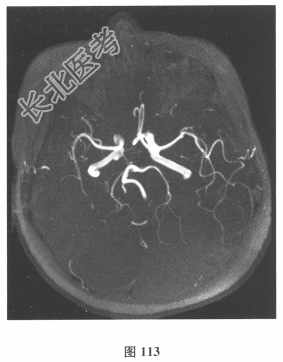

- 简答题2、脑脊液检查:常规、生化均正常,CSF-病毒TORCH(-),抗Hu、Yo、Ri均阴性,OB、MBP正常。血清抗Hu、Yo、Ri均阴性。颅脑MRI显示左颞枕、右顶枕多发长T₁、长T₂信号,Flair高信号,病变累及皮质及皮质下白质,病灶无强化,见图108~图114。根据颅脑MRI,需要鉴别的疾病应是